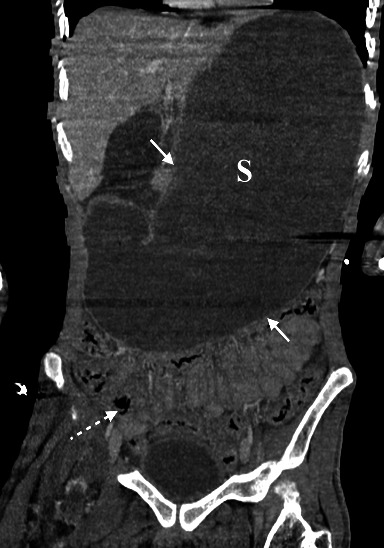

肠系膜上动脉综合征(SMAS)是一种罕见的不寻常疾病,经临床怀疑和放射学证实。由于腹腔内脂肪减少,十二指肠第三部分与腹主动脉(AA)和肠系膜上动脉(SMA)之间发生撞击,继发十二指肠梗阻。高发病率和高死亡率与漏诊或晚诊有关,而漏诊或晚诊可导致胃穿孔和胃出血等并发症。我们介绍了一例 33 岁的男性病例,他以前并不知道自己患有 SMAS,因出现脓毒性休克症状而到急诊科就诊,主诉发烧和呼吸道症状持续数天。检查结果显示,吸入性肺炎继发于上消化道梗阻,计算机断层扫描(CT)显示有 SMAS 征象。病情急剧恶化导致心脏骤停并死亡。通过这篇文章,我们强调了早期正确诊断 SMAS 的重要性,因为没有一个数字是严格意义上的诊断,必须根据临床病史和体格检查来解释放射图像,所以诊断 SMAS 有时很困难。

Superior mesenteric artery syndrome (SMAS) is a rare and unusual disease, suspected clinically and confirmed radiologically. It represents a duodenal obstruction secondary to the impingement of the third portion of the duodenum between the abdominal aorta (AA) and the superior mesenteric artery (SMA) due to decreased intraabdominal fat. High morbidity and mortality rates are linked to missed or late diagnosis that can lead to complications, such as gastric perforation and gastric hemorrhage. We present the case of a 33-year-old man who was not previously known to have a SMAS, who presented to the emergency department with signs of septic shock, complaining of fever and respiratory symptoms for several days. Investigations showed aspiration pneumonia secondary to an upper gastrointestinal obstruction with signs of SMAS on a computed tomography (CT) scanner. Acute and rapid deterioration led to cardiac arrest and death. Through this article, we highlight the importance of early and correct diagnosis of SMAS which can sometimes be challenging, since no number is strictly diagnostic and radiological images must be interpreted in light of the clinical history and physical examination.